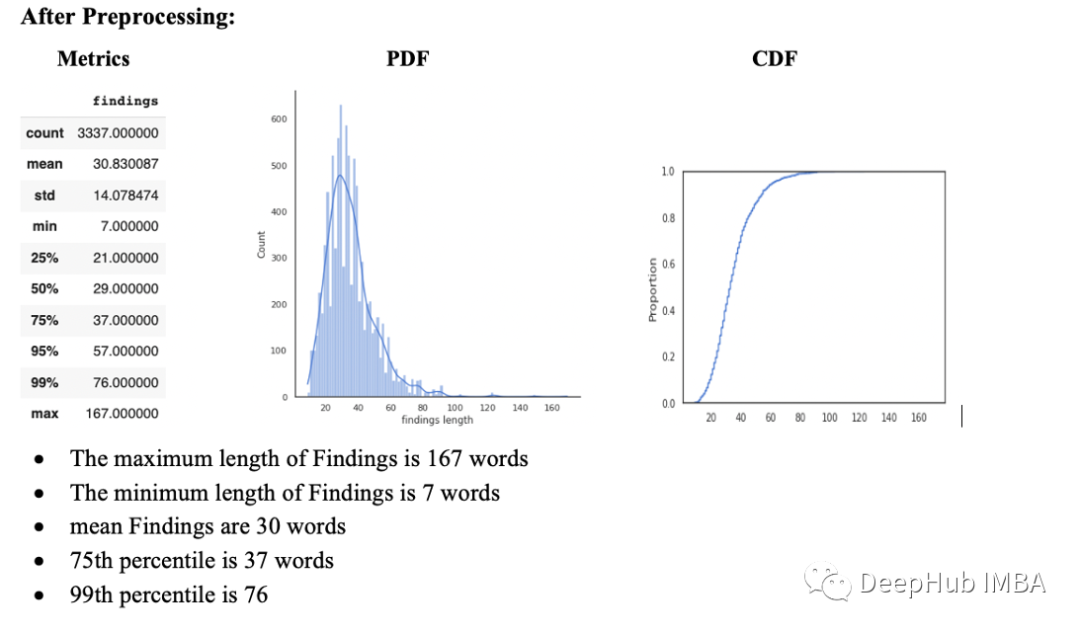

理解统计结果